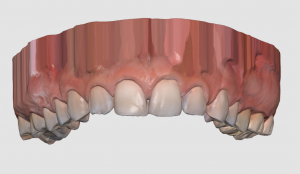

A Medit i500 scan was taken and merged with a CT scan and the distance to bone was measured (5.5 mm’s) giving enough space for soft tissue contouring with a diode laser. The 3D X-ray must be captured with cotton rolls placed in the vestibule so that you can differentiate between the gingiva and the lip. Ideally you should not close the base of the digital model by the intra-oral scanner as it can make the merge of the data sets more difficult than it needs to be.

A Medit i500 scan was taken and merged with a CT scan and the distance to bone was measured (5.5 mm’s) giving enough space for soft tissue contouring with a diode laser. The 3D X-ray must be captured with cotton rolls placed in the vestibule so that you can differentiate between the gingiva and the lip. Ideally you should not close the base of the digital model by the intra-oral scanner as it can make the merge of the data sets more difficult than it needs to be.